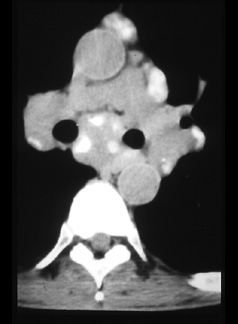

There is an enlarged right paracardiac lymph node (arrows). CT shows more lymph nodes than radiographs and more accurately locates the nodes. This is important in deciding which procedure should be used; mediastinoscopy, bronchoscopy, Chamberlin procedure, or percutaneous biopsy, if it is necessary to biopsy a node. |